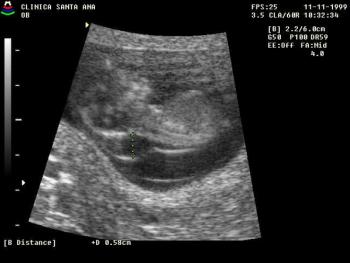

Mother is sure of LMP 17th Nov/98 ( EDD = 24/8/99). On ultrasound scan (17/7/99) the average gestational age is only 31 weeks, ie the ultrasound derived EDD=18/9/99.